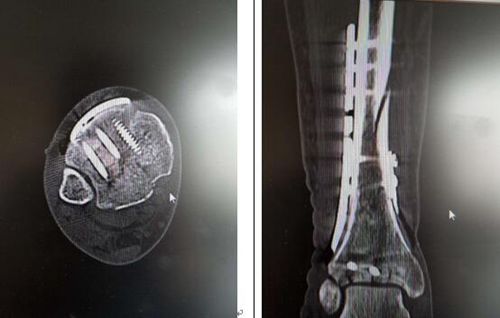

在行至Matteo病床時(shí),考慮到其病情較為嚴(yán)重。在與王旭主任溝通后,王旭主任決定與曹廣超主任團(tuán)隊(duì)一起為Matteo實(shí)施雙pilon骨折切開復(fù)位內(nèi)固定術(shù),手術(shù)順利完成。

曹廣超主任說,“這臺(tái)手術(shù)做得非常好。目前,患者傷口恢復(fù)良好。”經(jīng)過兩周的觀察,Matteo已于昨日出院回家。